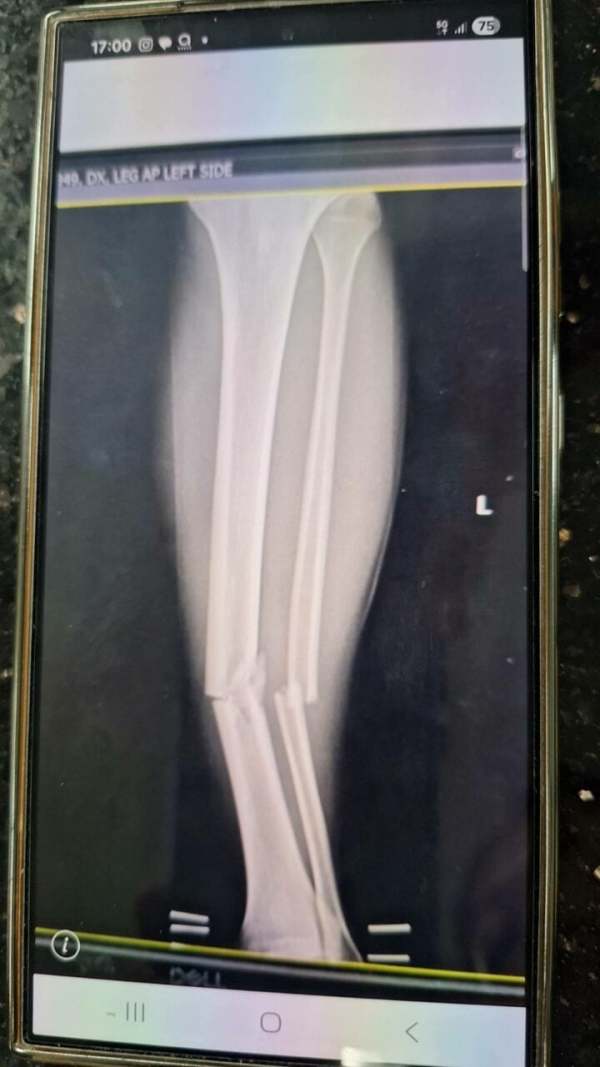

จากนั้น ทีม พราม แบงค็อก ได้โพสต์ภาพผลสแกนขาของ ไชยพฤกษ์ ปรากฏว่า ท่อนขาหัก ขณะที่เจ้าตัวยังทำใจแข็ง ยิ้มได้ พร้อมกันนี้ พราม ยังขึ้นข้อความว่า “บทเรียนที่ไหน? จะสอนใครได้? ถูกทำร้ายในสนาม! ได้แค่ใบเหลือง?!? ไม่แปลก! ทีมชาติไทย ขาดแคลน”